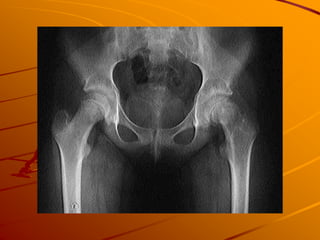

Slipped Capital Femoral Epiphysis

(SCFE – pronouced Skiffy)

Overweight 10-16 yo Boys or 12-14 yo Girls

History

– Vague Knee pain with no trauma

Exam – pain on internal rotation of hip

Diagnosis – Xray AP/Lat view of Pelvis and b/l

hips

Treatment –

– Immediate Cessation of weightbearing

– Surgical stabilization

Take Home Point – ALWAYS EXAMINE HIP IN

KIDS WITH KNEE PAIN